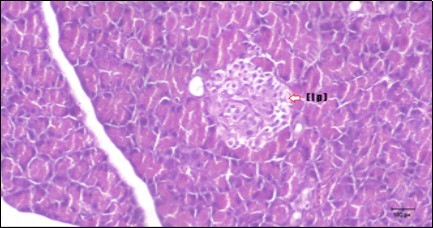

Pancreas Histopathological Observations

Histological examination of pancreas of the control rats showed normal sized islets of pancreas (Ip) compared to the diabetic rats which showed markedly atrophic islets of pancreas (I.p.) (Figure 8 and Figure 9). Pancreas of in groups (3) and (4) rats showed mild atrophic islets of pancreas (I.p.) with inflammatory cellular infiltrate (Figure 10 and Figure 11). The pancreas of rats in group (5) showed nearly normal islets of pancreas (I.p.) with few inflammatory cellular infiltrate (I.c.) (Figure 12).

Figure 9.Photomicrogragh of pancreas section of diabetic rat showing the markedly atrophic islets of Langerhans. (arrow) (H&E) (40X).

Figure 10.Photomicrogragh of pancreas section of treated rat with Fenugreek showing less improved islets of Langerhans with more cells (star). (H&E) (40X).

Figure 11.Photomicrogragh of pancreas section of treated rat with Glimepiride showing mildly improved of isled of Langerhans with large number of cells (dashed-arrow). (H&E) (40X).

Figure 12.Photomicrogragh of pancreas section of treated rat with both Fenugreek and Glimepiride showing nearly normal islets of Langerhans with spindle (arrow) & polygonal cells (dashed- arrow). (H&E) (40x).

Histopathological observation in diabetic control showed degenerative changes in both endocrine and exocrine pancreases. A probable explanation may be related to oxidative stress resulting from hyperglycemia which decreases the antioxidants levels and increases ROS 33 and the activities of antioxidant enzyme were altered in diabetic rats. These effects further exacerbate the development and progression of diabetes complications and these may represent the causes of degeneration revealed in histological sections. Fenugreek improved blood glucose levels and insulin, lowered pancreatic islet and β-cells damage which may be attributed to its immune modulatory activity and insulin stimulation action along with its antioxidant potential 32. Glimepiride caused restoration of morphology of beta cell of diabetic and it increased percentage of beta cells 34. This protective effect could be attributed to the antioxidant properties of Glimepiride. Combination therapy improves the protective effect of both therapies alone.